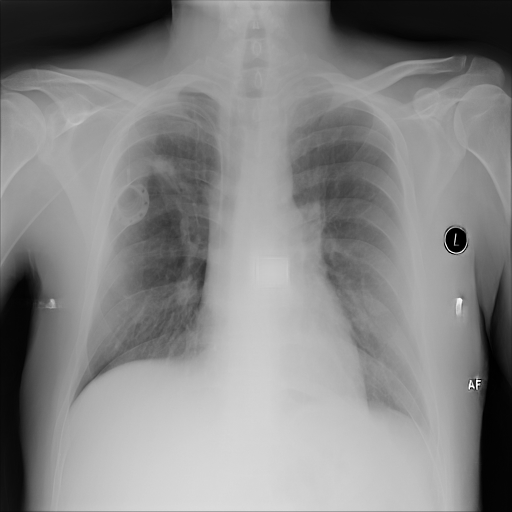

In Fig. 1, we show four ϵitalic-ϵ\epsilon-LDP-processed CXR images of clinical cases obtained with the image domain LDP, which directly imposes the Laplace mechanism on the input image, with different privacy budgets together with the original images. Fig. 2 shows four ϵitalic-ϵ\epsilon-LDP-processed CXR images of clinical cases obtained with DP-GLOW and different privacy budgets together with the original images. In case 1 for DP-GLOW, there is decreased permeability in the bilateral hilar regions. Although this hilar opacity tends to be preserved with a larger privacy budget, the entire image is degraded when the privacy budget becomes 101HWsuperscript101𝐻𝑊10^{1}\cdot H\cdot W. A similar tendency is observed in the images of all the four cases for DP-GLOW; for example, in case 4 with ϵ=101HWitalic-ϵsuperscript101𝐻𝑊\epsilon=10^{1}\cdot H\cdot W, the lung opacity suggesting pneumonia in the right lower lung field is well preserved, while the entire image is degraded.